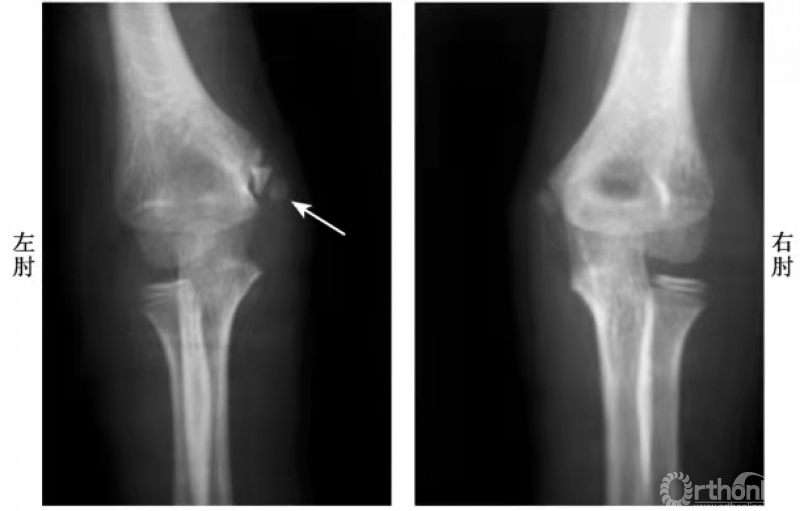

例:内上髁骨骺并带一皮质骨片略下移位(图3)

图3

例1:内上髁骨骺分离并带一模糊的骨皮质,并向外侧旋转,而达关节水平(图4)。

图4